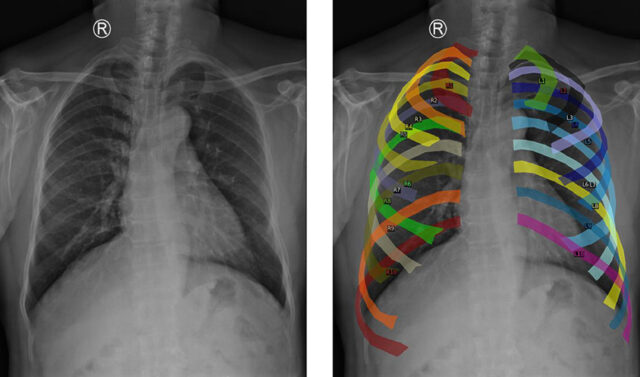

El modelo, denominado Mamba-YOLOvX, es capaz de identificar alteraciones de manera precisa y rápida, aprovechando algoritmos avanzados de aprendizaje automático y redes neuronales convolucionales. Estas tecnologías imitan el proceso de percepción visual humano, permitiendo al sistema aprender y reconocer anomalías en múltiples radiografías.

Además, este modelo no sólo examina los detalles locales, sino que también toma en cuenta el contexto global de la imagen. De esta manera, puede discriminar información irrelevante y concentrarse solo en las áreas que requieren atención.